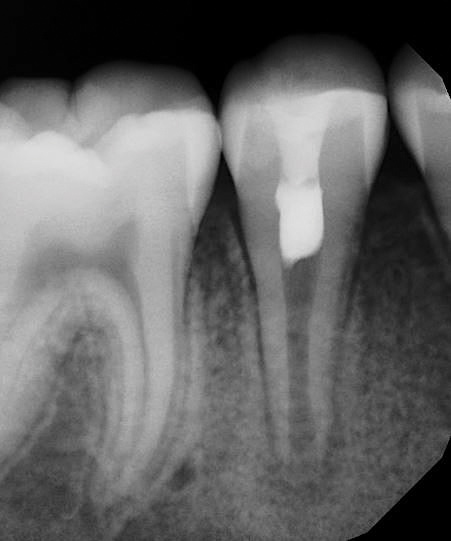

At the final regenerative endodontic treatment appointment, a 3% mepivacaine solution without a vasoconstrictor is used to obtain local anesthesia (the lack of a vasoconstrictor will allow for periapical bleeding). A rubber dam is placed, and after the tooth is accessed, 17% EDTA is used to irrigate the canal in conjunction with files to remove the calcium hydroxide and prepare the dentin. Next, the canal is dried, and bleeding is induced with a hand file 1 to 2 mm beyond the apical foramen. The blood should be stopped at a level in the canal (ie, cementoenamel junction) that will allow for the placement of 3 to 4 mm of restorative material (Figure 2). The induction of periapical bleeding into the canal space is necessary in regenerative endodontic procedures. The induced bleeding supplies scaffolding, stem cells, and blood-derived bioactive growth factors. These growth factors supplement the growth factors embedded in the dentinal matrix that are released when the 17% EDTA is irrigated into the canal.20-22 It has been shown that the stem cells from the apical papilla and the growth factors released from the dentin demonstrate an increased survival rate with the use of EDTA and calcium hydroxide.22 In contrast, the use of high concentrations of sodium hypochlorite and antibiotic paste have been shown to result in decreased stem cell and growth factor survival.23 The triad of stem cells, scaffolding, and growth factors is what enables the tissue regeneration to occur.24

(2.) The induction of canal bleeding after file insertion 1 to 2 mm beyond the apical foramen.

Figure 2